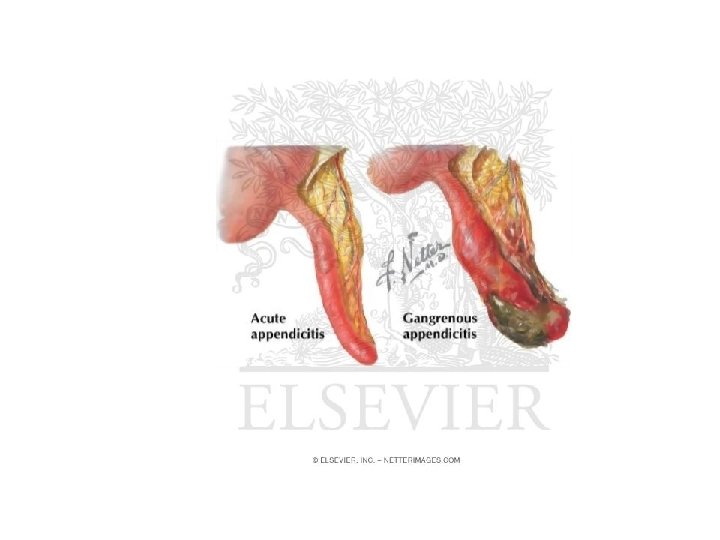

• Kanali i bllokuar zgjerohet, tendoset, krijohet staze e qarkullimit te linfes, iskemi, mikroinfarkte deri ne gangrene te apendiksit. • Ketu ndodh edhe invadimi bakterial i hapesires apendikulare dhe inflamacioni I cili zhvillohet shtrese pas shtrese me hiperemi e deri ne infiltrim purulent.

• - KOMPLIKACIONET: Appendix i gangrenizuar Perforim i appendix-it Peritonitis Abscess Sepsis